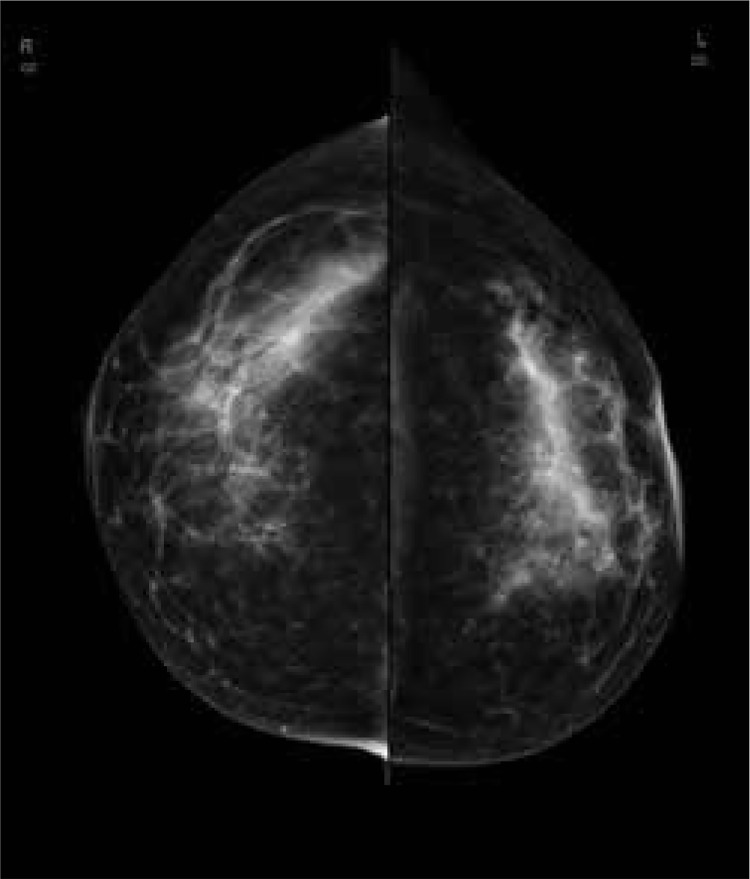

Purpose: This single-centre study includes a comparative analysis of the diagnostic performance of contrast-enhanced mammography (CEM) and automatic breast ultrasound (ABUS). The study involved 81 patients with focal breast lesions, who underwent ABUS, full-field digital mammography (FFDM), and CEM.

Material and methods: A total of 169 focal lesions were found in 81 patients, of which 110 lesions were histopathologically verified, 92 were malignant, 5 were B3 lesions, and 13 were benign. On CEM 19 additional lesions not visible on other imaging examinations were found, and as many as 36 new lesions were detected on ABUS. The number of lesions detected in patients with multiple lesions were 106 from 169 on ABUS, 65 on FFDM, and 88 on CEM. The highest correlation between the lesion's margin and its histopathological character was found in FFDM (p < 0.00), then ABUS (p = 0.038), and the lowest in CEM (p = 0.043). Compliance in determining the lesions' size comparing to histopathology as a gold standard was the highest for ABUS (p = 0.258) and lower for CEM (p = 0.012).

Results: The sensitivity of ABUS, FFDM, and CEM was, respectively: 80.43, 90.22, and 93.48; specificity: 27.78, 11.11, and 11.11; positive predictive value (PPV): 85.06, 83.84, and 84.31; negative predictive value (NPV): 21.74, 18.18, and 25; and accuracy: 71.82, 77.27, and 80. The sensitivity and accuracy of the combination of FFDM and ABUS were, respectively, 100 (p = 0.02) and 84.55 (AUC = 0.947) and for the combination of FFDM + CEM 93.48 (p = 0.25) and 79.09 (AUC = 0.855).

Conclusions: The study confirms that both ABUS and CEM may serve as a valuable complementary method for FFDM.